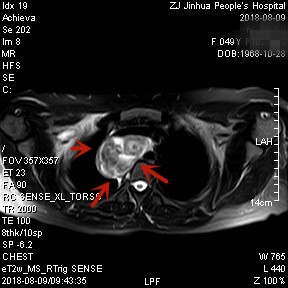

上图均示MRI下的肿瘤情况,红色箭头示肿块

上图示颈部与胸内的病灶关系密切,但绿色箭头处似有分界,仅少许相连